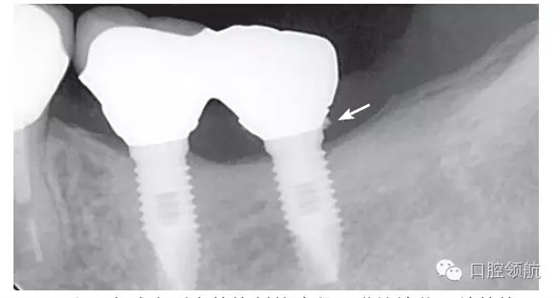

使用多種配件的螺絲固位的修復(fù)方式,必須有高精度的技工技術(shù),使用多種基臺(tái)配件,高精度的制作,技工的加工費(fèi)用等會(huì)帶來(lái)較高的經(jīng)濟(jì)負(fù)擔(dān),但這是臨床上無(wú)法回避的問(wèn)題。一方面,期待“粘接”材料和技術(shù)的進(jìn)步;另一方面期待金屬和瓷能有長(zhǎng)期穩(wěn)定的結(jié)合效果?,F(xiàn)在,介紹一種先將上部基臺(tái)和上部修復(fù)體粘接固位后,再用螺絲固位的方法(圖5)。

圖5 氧化鋯基臺(tái)和氧化鋯冠用粘接劑固位,粘固形成一個(gè)整體后,再用螺絲固位,這樣比較起來(lái),剩余粘接劑的問(wèn)題得以解決,但螺絲孔產(chǎn)生的美學(xué)問(wèn)題也出現(xiàn)了。使用氧化鋯材料大致能解決此問(wèn)題。